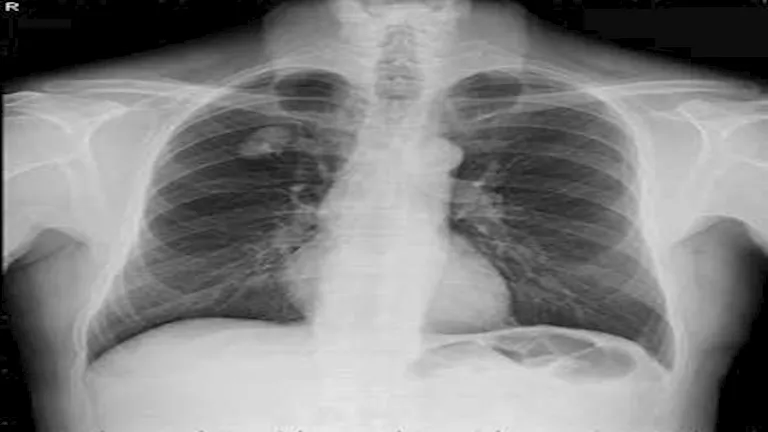

في أروقة مختبرات المستشفيات وعدسات الأطباء داخل أقسام الطوارئ، ظهرت نتائج تحاليل طبية وصفت بـ”الخارجة عن المألوف”، بعضها وصل حد الصدمة لما يحمله من أرقام غير قابلة للتصديق، وهذه الحالات، رغم ندرتها، تبقى بمثابة لغز يستفز العقل ويزيد من شأن المتابعة الطبية الاحترافية.

“أغرب نتيجة تحليل رأيتها في حياتي”.. بهذه الكلمات وصف أحد مراكز التحاليل الطبية عبر “فيسبوك” حالة غريبة وردتهم من مريض أرسل صورة نتيجة فحصه طالبًا تفسيرها، وسط حالة من الارتباك والدهشة، إذ بدت الأرقام غير منطقية وغير قابلة للفهم.

وما زاد من غرابة الموقف أن الطبيب المعالج شخص الحالة على أنها إصابة بفيروس كورونا، رغم أن مؤشرات التحليل لا تحمل أي دلالة واضحة على ذلك، وفق ما أفاد المركز.